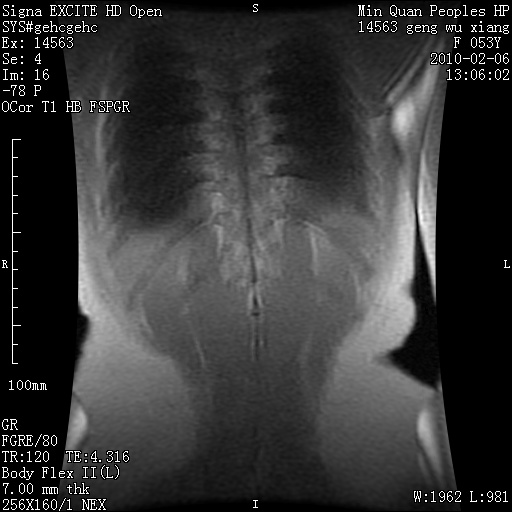

标题: MRI2762:胆道梗阻原因?

f,53y,全身黄染多日。

高位胆道梗阻 胆管癌可能性大

支持 高位胆道梗阻 胆管癌可能性大。